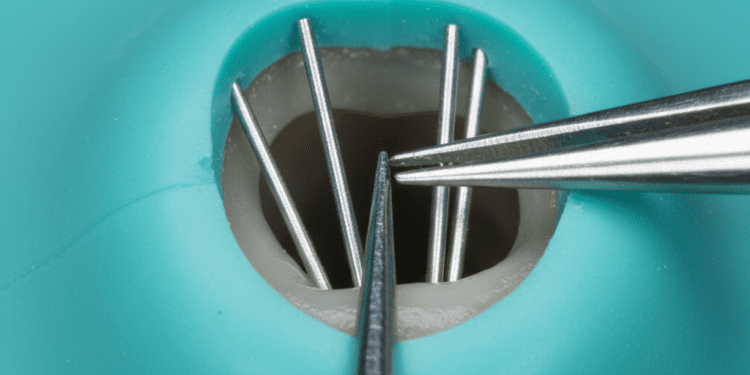

Raízes dentárias

As raízes podem variar em número e formato dependendo do tipo de dente e da arcada (maxilar ou mandibular). Em geral:

- Incisivos e caninos normalmente possuem uma única raiz cônica.

- Pré-molares podem ter uma ou duas raízes, dependendo do dente e da arcada.

- Molares geralmente apresentam múltiplas raízes, que podem variar de duas a três raízes, a fim de oferecer maior estabilidade.

As raízes são revestidas externamente pelo cemento e se conectam ao osso alveolar pelo ligamento periodontal, formando a base estrutural que mantém o dente fixo na boca.

Vascularização e inervação

A polpa dentária é altamente vascularizada e inervada. Os vasos sanguíneos e os nervos entram pela raiz através do forame apical, localizado na extremidade da raiz, e se ramificam dentro do canal radicular.